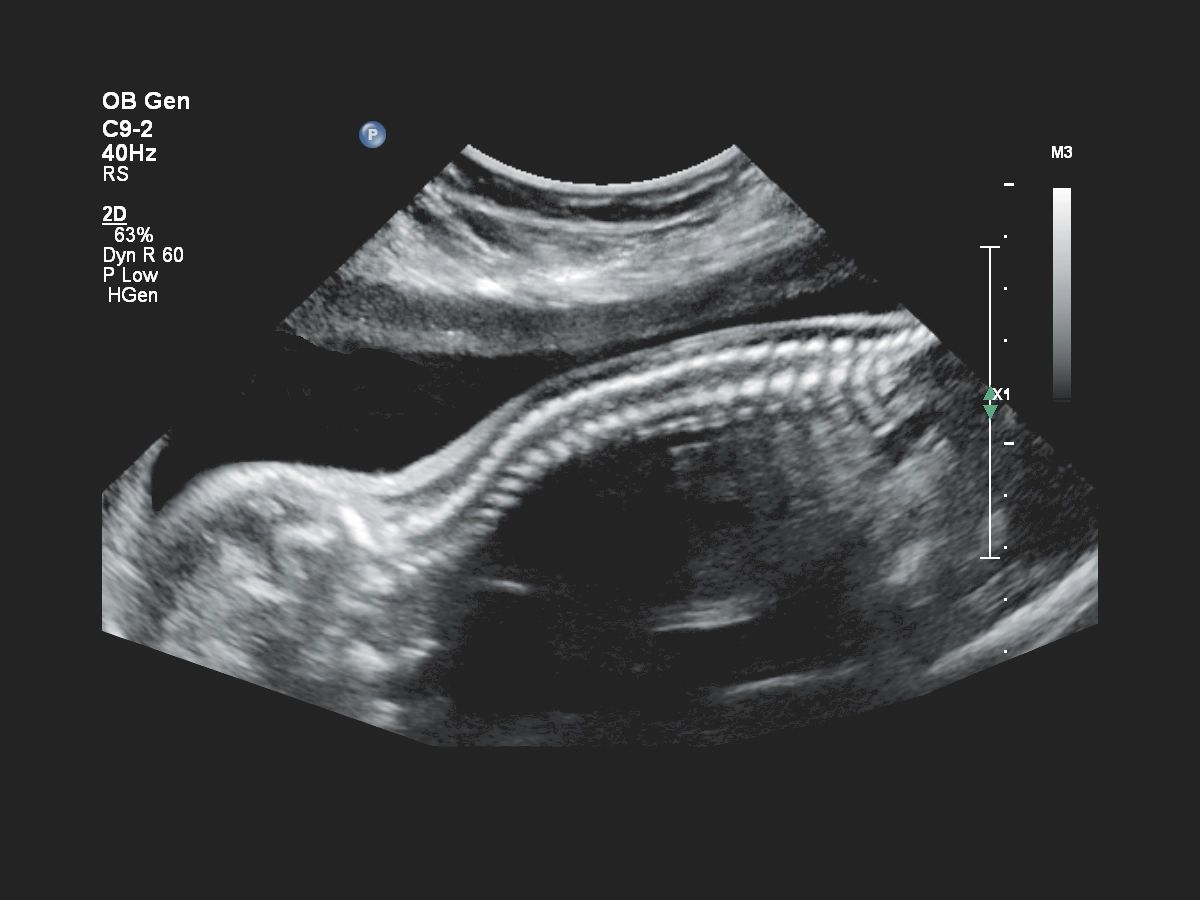

- Акушерство

- Fetal Heart Navigator - функция для навигации сердца плода

- aBiometry Assist - автоматические биометрические измерения

- Навигатор для УЗИ-сердца плода FHN